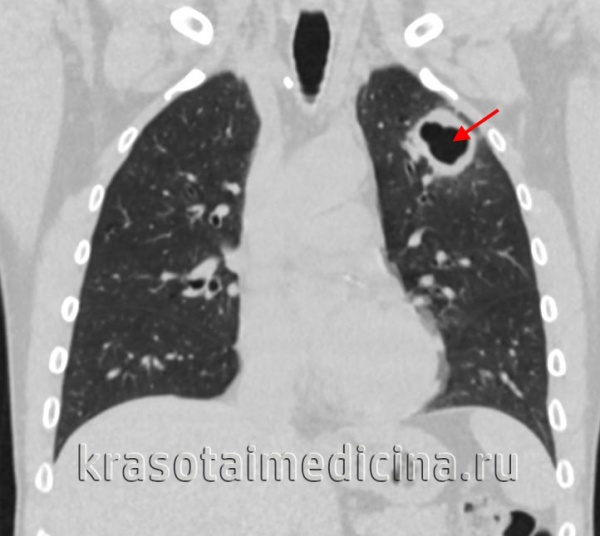

Поводом для неправильного заключения становится, кроме того, некоторое своеобразие рентгенологически определяемых изменений в легких у пожилых людей, что обусловлено отчасти аденобронхогенным развитием процесса. В этих случаях отмечаются инфильтрация и расширение корней легких, а очаговые и фокусные образования чаще, чем у лиц более молодого возраста, локализуются в 3-м, 6-м, 7-м и 10-м сегментах. Определяется при этом и среднедолевой синдром, а также реактивные изменения в междолевой, медиастинальной или костальной плевре. При такой картине нередко возникает подозрение на наличие у больного пневмонии или рака легкого. Только при тщательном клинико-рентгенологическом, бронхиологическом и лабораторном исследовании можно избежать ошибочного заключения о природе болезни.

У пациентов, перенесших туберкулезный плеврит, лечение с помощью искусственного пневмоторакса или хирургической торакопластики, развивается плеврогенный цирроз: при этом соединительная ткань прорастает в легочную паренхиму из утолщенной плевры. Цирротическим туберкулезом легких может осложняться туберкулез ВГЛУ, первичный туберкулезный комплекс, туберкулез бронхов. При этих формах пневмофиброз развивается в результате обтурации бронха в ателектатическом участке (чаще в язычковых сегментах левого легкого, верхней или средней доле правого легкого). Такой механизм патогенеза носит название бронхогенного цирроза.

- Рентгенография легких. На рентгенограммах обнаруживается затемнение пораженной доли или сегментов, патологически измененный участок легкого уменьшен в размерах. На фоне затемнения могут выделяться более светлые участки (бронхоэктазы, каверны). Плевра утолщена, тень средостения смещена в сторону поражения. Особенно четко описанные изменения видны на томограммах. Ранее для выявления изменений со стороны бронхов в зоне цирроза широко использовалась бронхография, однако в настоящее время ее успешно заменяет КТ легких.